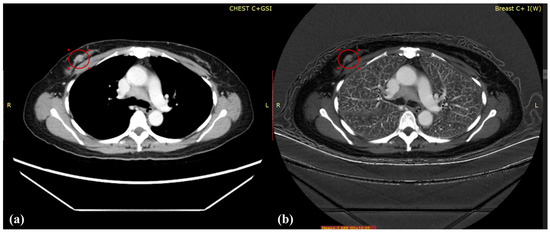

Dual-Energy Computed Tomography for Evaluation of Breast Cancer Follow-Ups: Comparison of Virtual Monoenergetic Images and Iodine-Map

2.2. Image Acquisition

2.3. Image Reconstruction and Analysis